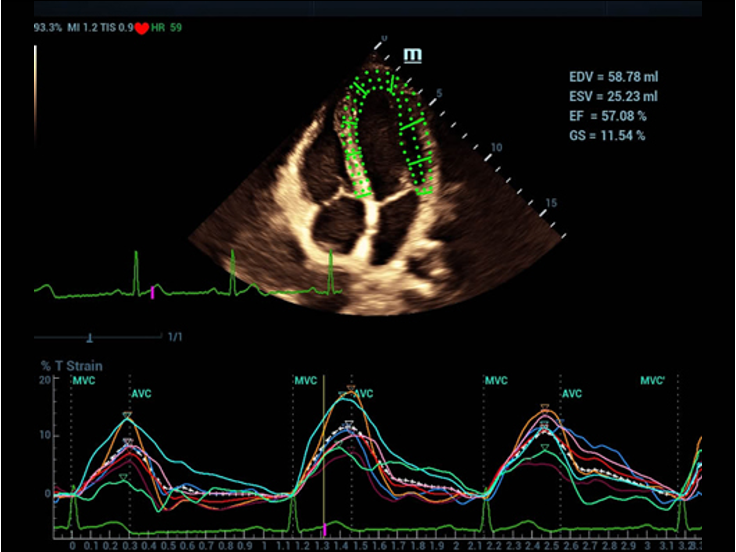

Rigurgito polmonare cardiaco

HCM cardiaca